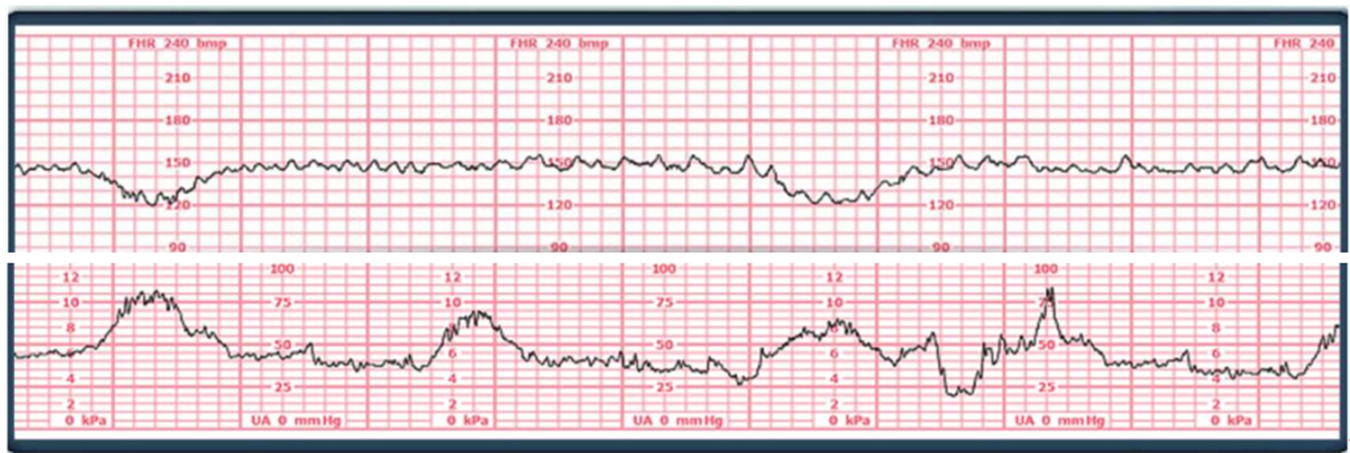

A 38 week primipara client comes into the clinic for a cervical check and an external monitor is placed on the client's abdomen.

Based on the following strip how would the nurse document the fetal heart rate.